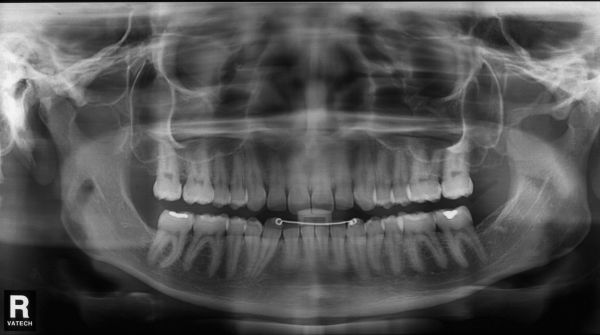

Tratamento da maloclusão de Classe III com elásticos intermaxilares e controle mecânico do arco inferior

Final